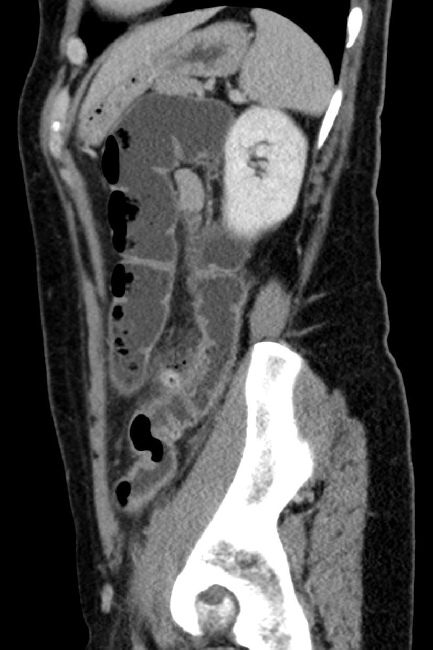

2. Welches der folgenden Organe ist auf dem sagittalen Bild nicht erfasst?

- a) Milz

- b) Leber

- c) Magen

- d) Niere

- e) Aorta

4. Welchen Befund notieren zu dem sagittalen Bild?

- a) Ausgedehnte freie intraabdominelle Luft, der ventralen Bauchwand angrenzend

- b) Ausgedehnte freie intraabdominelle Luft, besonders um die Leber

- c) Luftperlen in der Gallenblasenwand

- d) Einzelne Luftperlen ventral des Colon descendens

- e) Kein suspekter Befund, keine Luft außerhalb der Darmschlingen